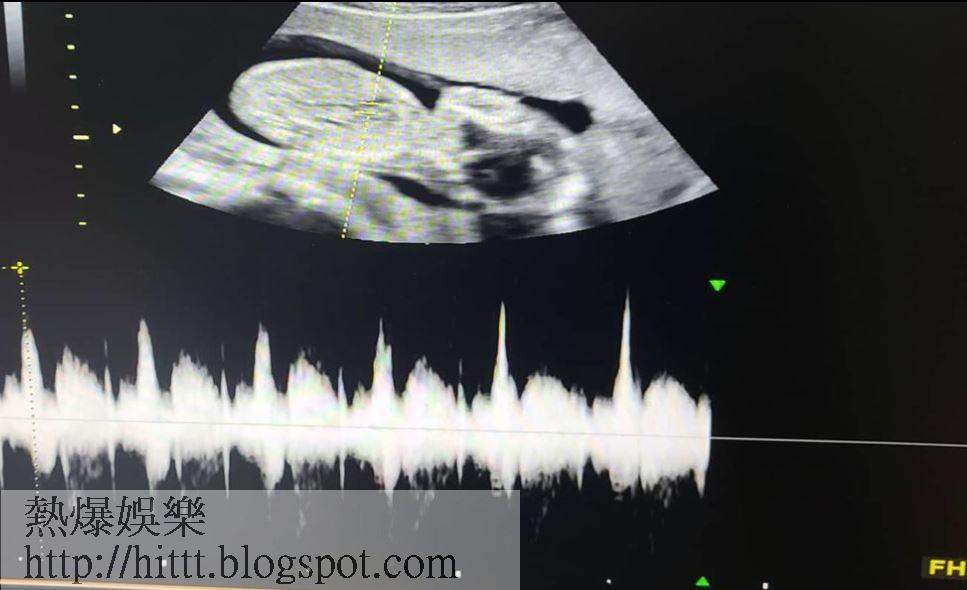

而目前懷孕20周的趙敏雅,昨日就公開超聲波照,宣佈陀慈菇椗的消息,表示自己隨時都能感覺到胎動,而且至今仍有孕吐。